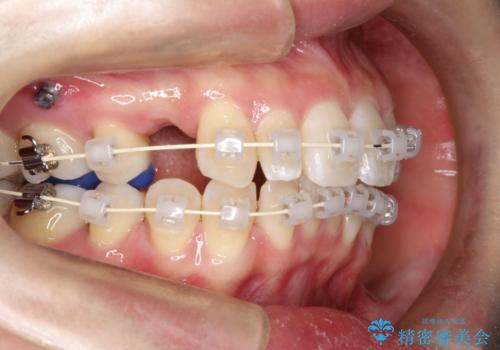

- 矯正装置

- 審美装置

上顎の歯が全体的に前方に位置しているのと、前から2番目の歯が通常よりも小さい矮小歯という状態でした。

出っ歯をなおすために上顎の前から4番目の歯を抜歯して、引っ込めるのと、前から2番目の歯に通常の大きさのオールセラミックを装着して整った歯並びにすることにしました。